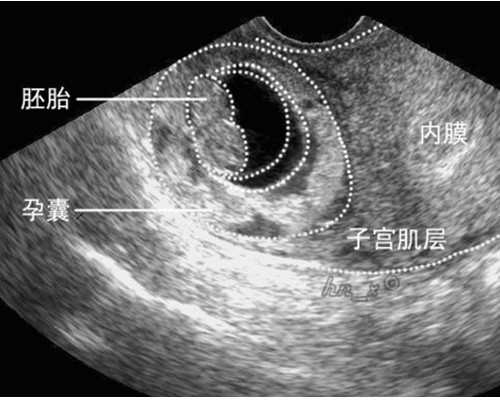

子宫后位不会影响胚胎着床,因此在美国试管婴儿移植时医生是在B超可视环境下进行,将胚胎移植到最利于着床的位置,不涉及到子宫位置。因此胚胎着床和子宫前位或是后位没有太大关系。

所以,子宫后位不会影响胚胎着床,因为在试管婴儿移植时医生是在B超可视环境下进行,将胚胎移植到最利于着床的位置,不涉及到子宫位置。